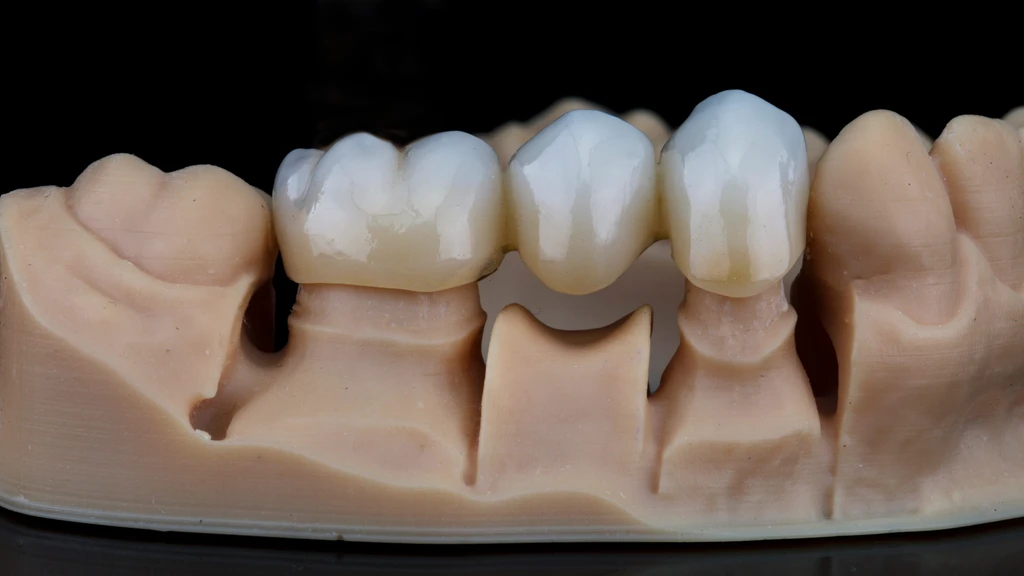

Dental Bridges

Dental bridges are also known as dental restorations and are comprised mainly of dental crowns which are attached to the sides of the abutment tooth. The dental crowns blend in perfectly with the abutment teeth and bridge the gap resulting in a natural appearance. The greatest advantage of using these dental bridges is their durability. They can last for many years if properly cared for.

A dental crown procedure is a rather simple dental treatment but one that requires a great deal of precision and expertise. All our procedures begin with an in-depth consultation.

Next, a cast of the patient’s teeth is taken to develop dental crowns perfectly customized according to the patient’s unique dental and bone structure. We want the dental crown to cover the affected tooth/teeth completely and blend naturally with the rest of the teeth. After the first appointment with us at our Katy dental clinic, the patient may be provided with temporary crowns until the time their final dental crowns are ready.